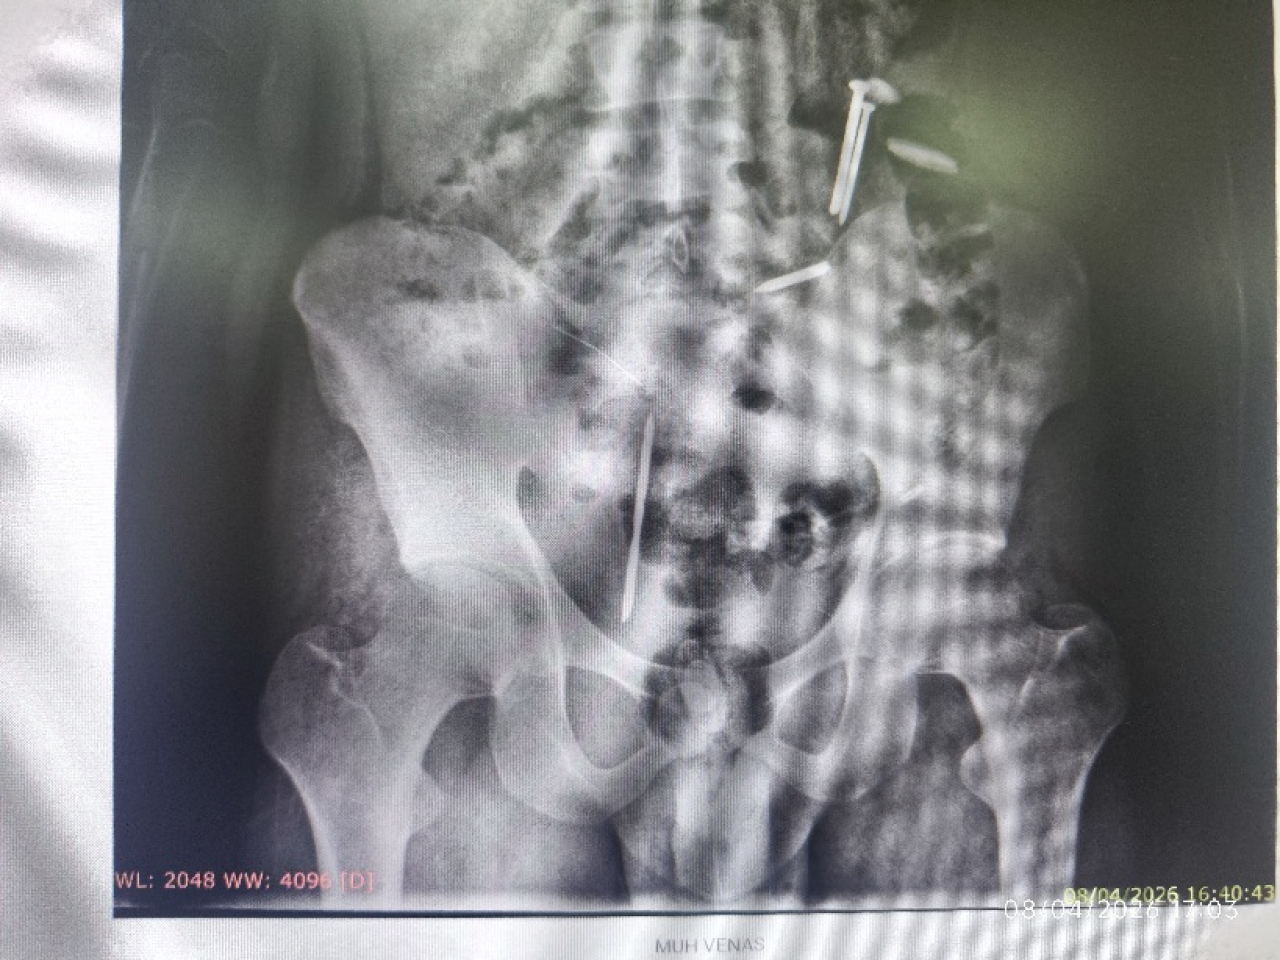

Hasil foto CT Scan terdapat logam mirip paku di tubuhnyaHasil foto CT Scan terdapat logam mirip paku di tubuhnya

Dari hasil pemeriksaan tersebut, tim medis menemukan beberapa benda asing di dalam tubuh pasien, di antaranya dua benda menyerupai paku, tiga benda logam lainnya, serta gumpalan berwarna hitam yang belum dapat diidentifikasi secara pasti.

“Jadi tadi saat proses medical check-up, seperti biasa dilakukan rontgen. Dari situ ditemukan benda-benda asing di dalam tubuhnya, bahkan ada juga yang berwarna hitam, kami belum bisa memastikan itu apa, apakah gumpalan darah atau benda lain,” ujar Roni saat dikonfirmasi lewat sambungan telepon, Rabu (8/4/2026) malam.